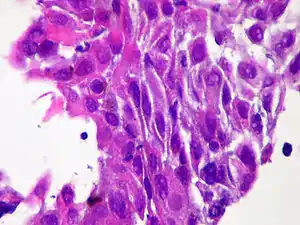

| Micrograph of squamous-cell carcinoma (H&E stain) | |

Squamous epithelial cells are not found in normal thyroid, thus the origin of SCTC is not clear. However, it might be a derived from the embryonic remnants such as thyroglossal duct or branchial clefts. Often SCTC is diagnosed in one of the thyroid lobes, but not in the pyramidal lobe. Another possible way of SCTC development can be through the squamous metaplasia of cells. However, that theory is also controversial, since the Hashimoto's thyroiditis and chronic lymphocytic thyroiditis (neoplasms to be showed squamous metaplasia) are not associated with SCTC. Primary STCT is usually diagnosed in both lobes of thyroid gland. The histopathology of STCT shows a squamous differentiation of tumor cells.